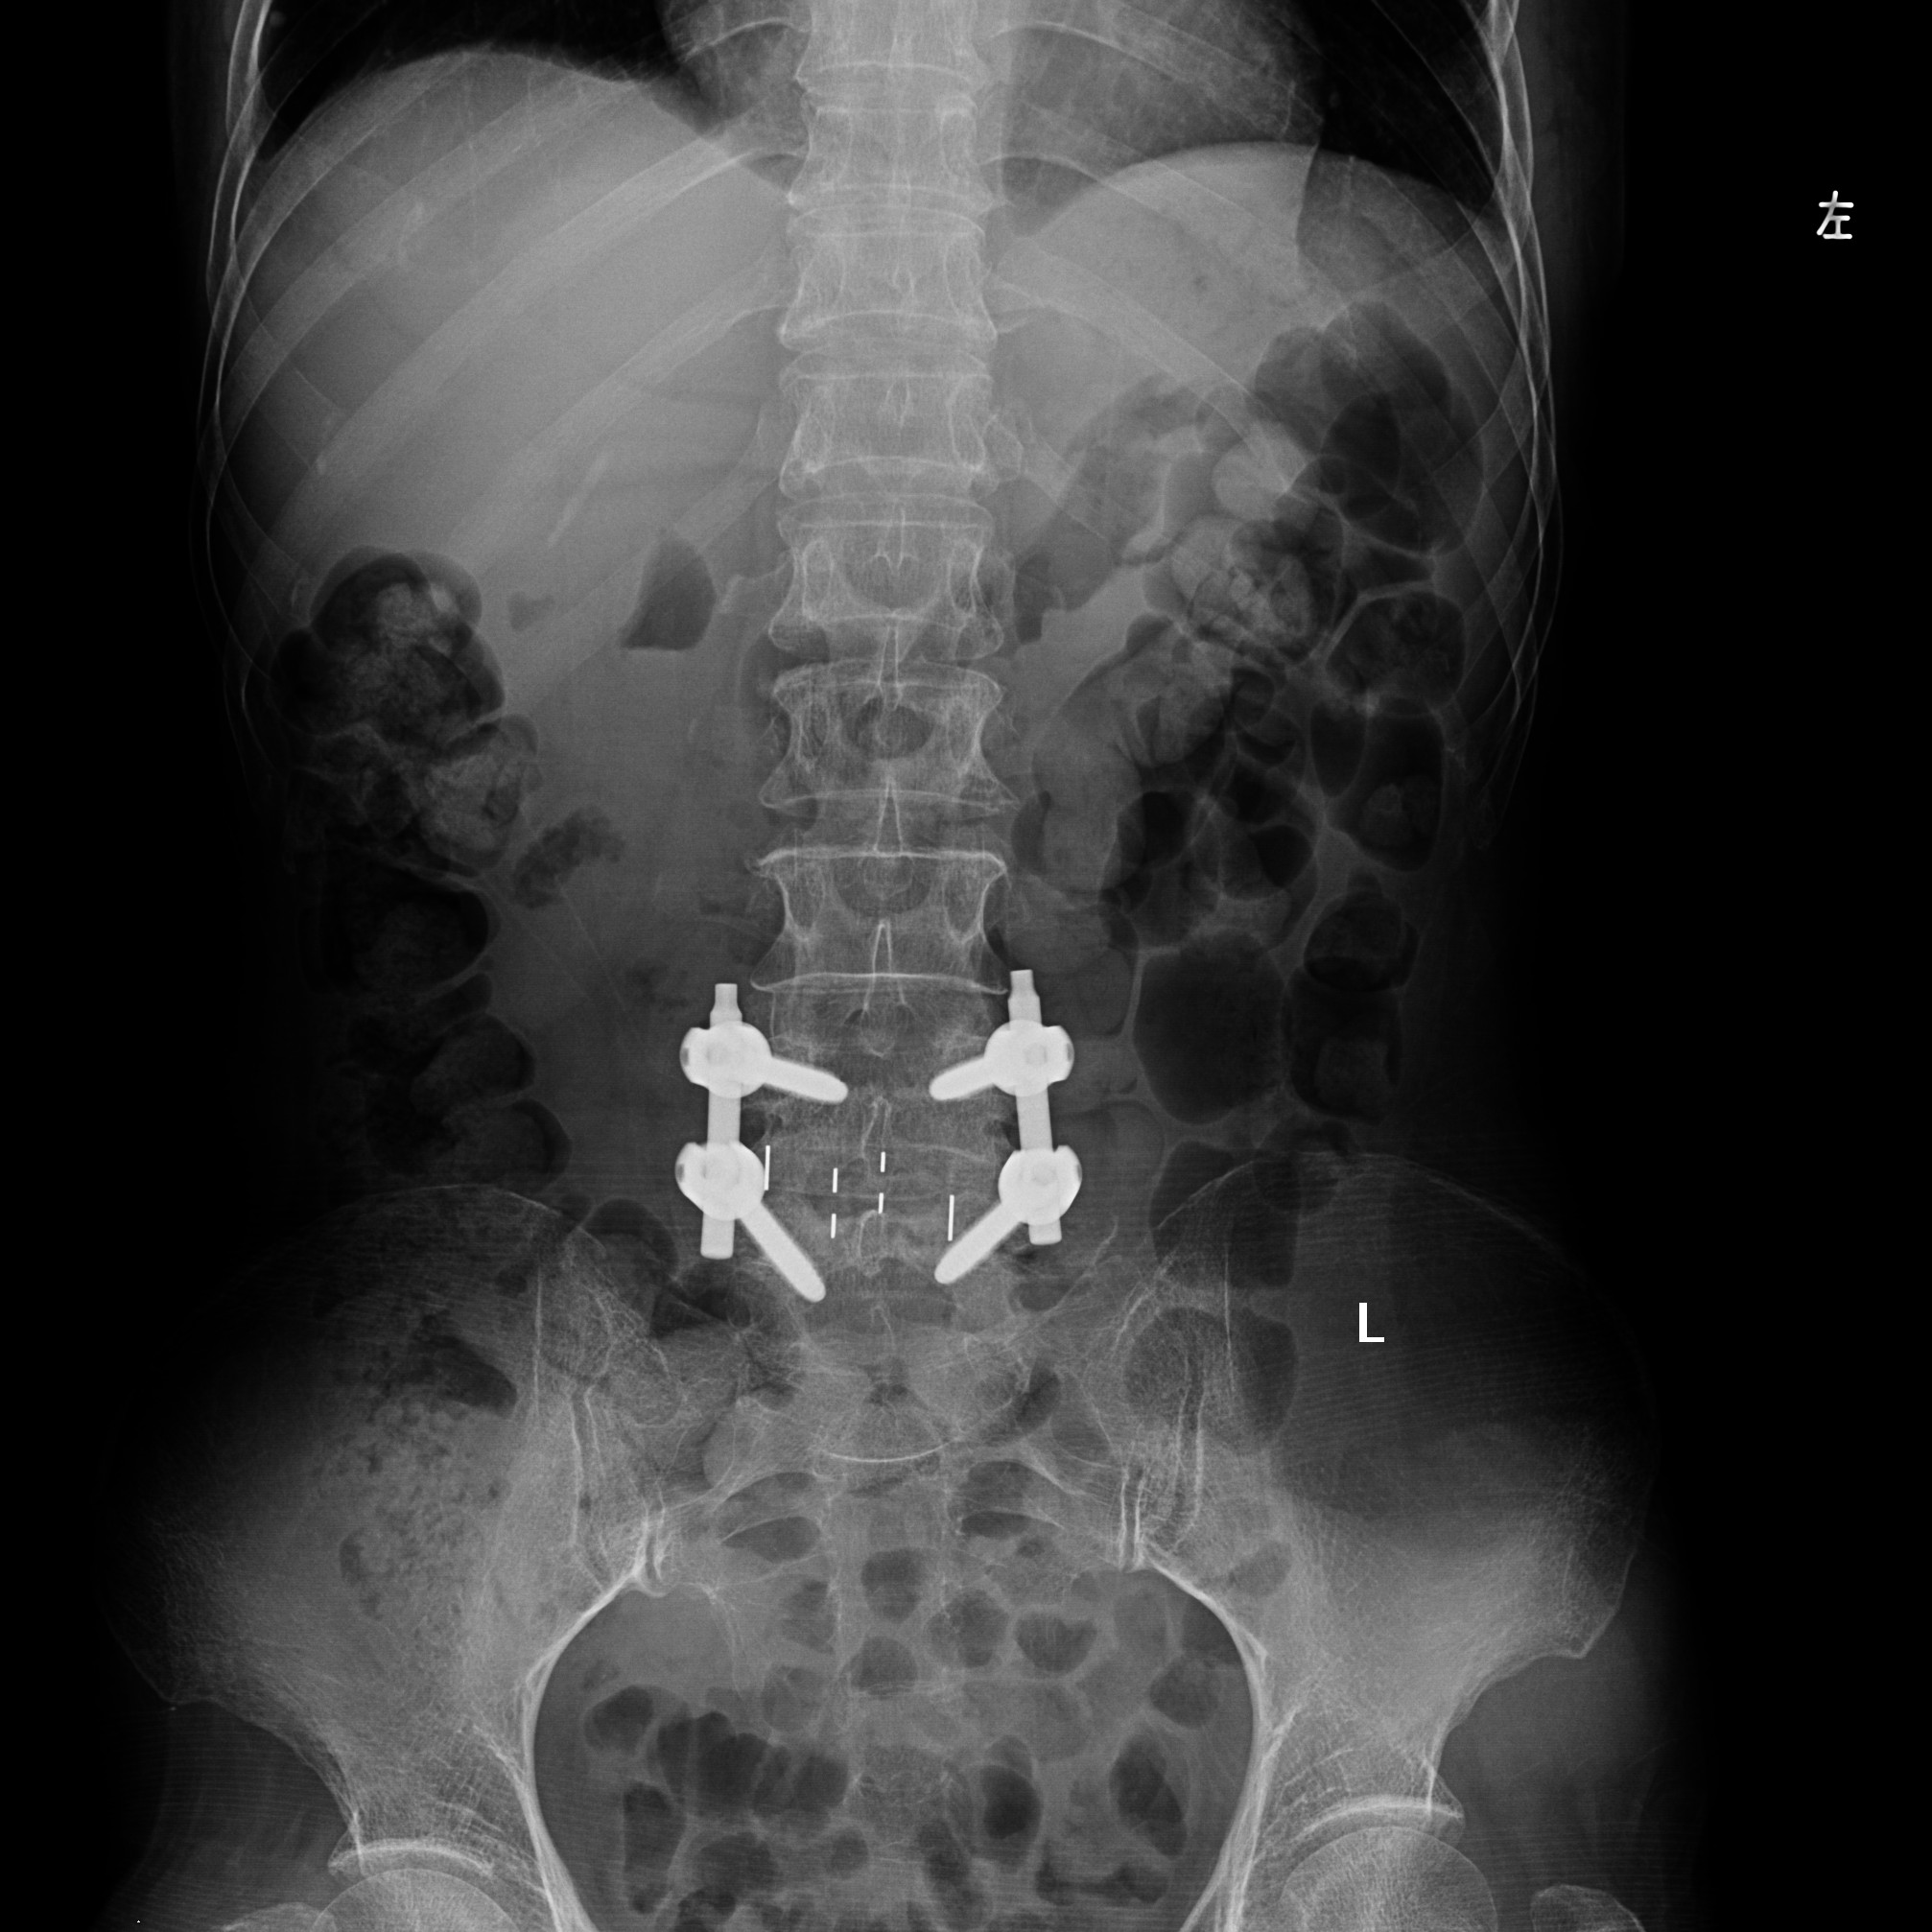

患者术后正面和侧面X-ray

我院脊柱外科团队经过科室会诊讨论后,决定采用微创腰椎斜外侧入路椎间融合术。以王剑龙主任、苗惊雷副主任医师、陈世杰主治医师及李劲松博士后组成的治疗团队在张朝跃教授、詹瑞森教授的指导下仔细分析病人的临床资料与影像学特点,进行了精心地术前准备,于12月4日上午9点开始手术。术中仅在患者左侧腹部椎体前缘2横指处做了一个约4cm的纵切口即可抵达手术部位,按照肌纤维方向钝性分离腹壁肌肉后到达腰椎侧前方,在主动脉与腰大肌间隙之间放置扩张通道,处理椎间隙并恢复间隙高度,使滑脱复位,放置合适大小的融合器。后路同样应用微创方法植入椎弓根螺钉固定。患者术后6天下床,腰痛及双下肢麻木症状完全消失。